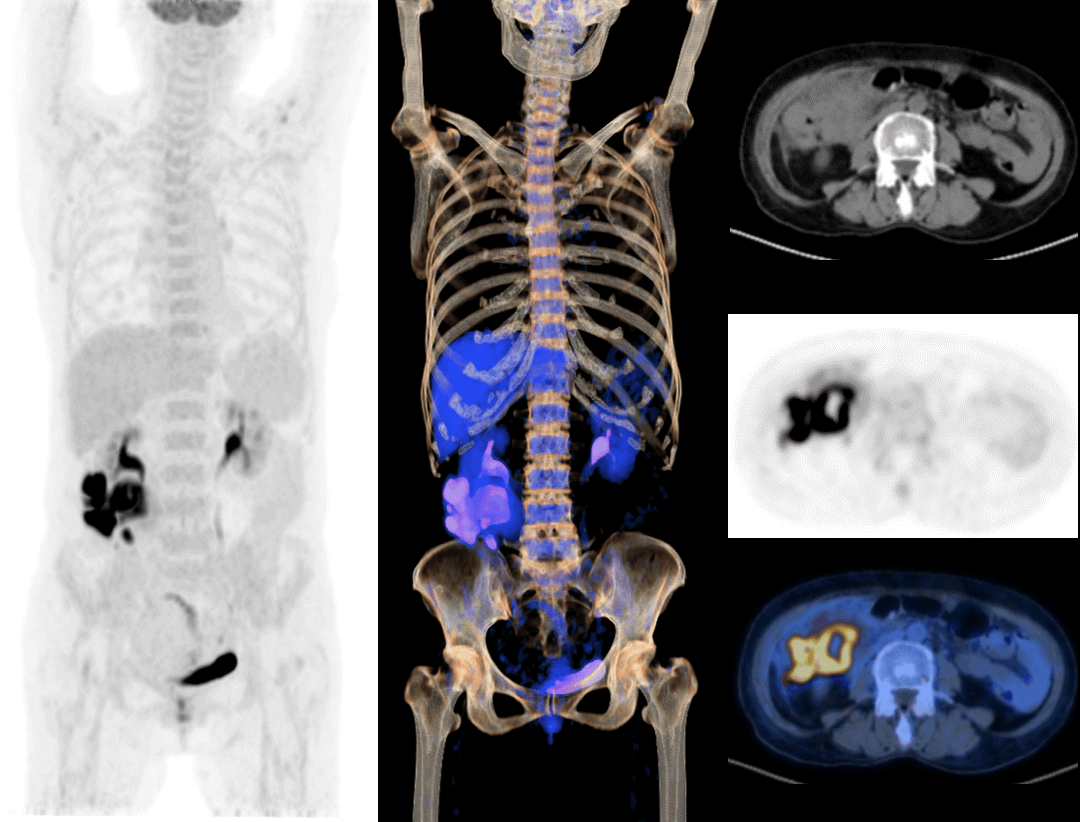

With the unique Integrated-Light-Guide Digital PET technology and a 160-slice CT system, uMI Vista combines high quality functional images with fine anatomical structure visualization. The state-of-the-art reconstruction technology and comprehensive applications further boost diagnostic precision in oncology, neurology and cardiology.

Clarity Imaging Chain

2.9mm NEMA Resolution

Outstanding resolution performance is achieved through systematic imaging chain engineering.

HYPER Iterative Reconstruction

Improves signal-to-noise ratio and contrast recovery to aid lesion detectability and quantitative accuracy.